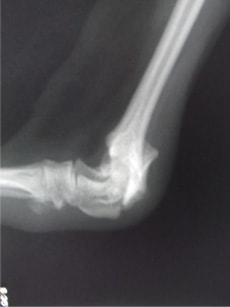

上腕骨外側上顆骨折 Salter Harris IV型 : 症例1 | 症例2

ペルシャ猫 11ヶ月齢 雄

他院にて左大腿骨遠位の成長板骨折(salter-harrisⅠ型)が認められており、治療相談を目的として来院。当院にて、キルシュナーワイヤーを用いたピンニングにより骨折部位の整復を行いました。術後の経過は良好で、現在も経過観察中です。

術前レントゲン

術後レントゲン